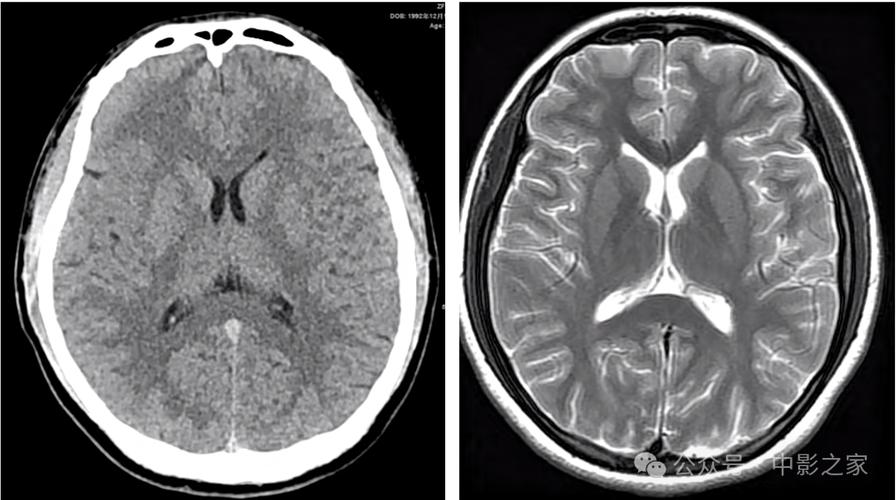

-

磁共振成像,特别是DWI序列(弥散加权成像)

- 这是目前诊断早期脑梗死的“金标准”,DWI对水分子的微观运动极其敏感,能在发病后30分钟到2小时内就发现缺血坏死的脑组织,表现为明显的高信号(亮点),而且边界清晰。

- 如果您或您的家人被怀疑脑梗死,但CT正常,医生一定会建议尽快做MRI检查。

CT血管造影

- 这是在CT基础上进行的增强扫描,可以清晰地显示颅内大血管(如颈内动脉、大脑中动脉等)有没有堵塞、狭窄或夹层,它能帮助医生找到病因,并评估是否适合进行溶栓或取栓治疗。

磁共振血管成像

(图片来源网络,侵删)与CTA类似,也是用来评估血管情况的,但无辐射,对血管壁的显示有时更优。